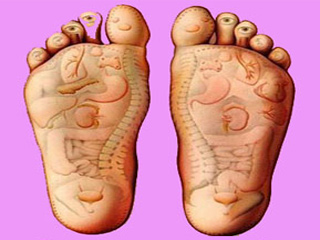

قیمت: 32٬000 تومان - دسته بندی فایل: علوم پزشکیپاورپوینت بازتاب شناسی REFLEXOLOGY

فروش ویژه پاور پوینت حرفه ای بازتاب شناسی REFLEXOLOGY با تخفیف استثنایی فقط 43 هزار تومان تعداد اسلاید: 18 اسلاید